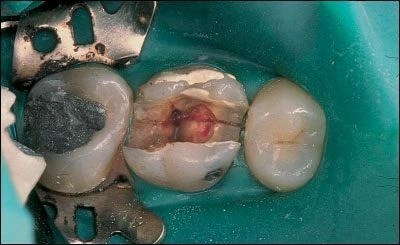

Kính hiển vi được dùng trong lĩnh vực y học trong nhiều năm qua, kính hiển vi nha khoa là một công cụ vô giá trong quá trình điều trị nội nha. Với khả năng phóng đại lên đến 25 lần, ánh sáng tuyệt vời, bác sĩ có thể quan sát những chi tiết trong thân răng và ngoài thân răng với độ chính xác cao. Đôi lúc một vết nứt có thể được nhìn thấy bên ngoài răng trước khi điều trị nội nha, sau khi mở xoang tuỷ độ sâu của nó cũng có thể quan sát được trong thân răng bằng kính hiển vi nha khoa.

– Tiên lượng trung bình: Nếu răng nhạy cảm khi thăm dò đường nứt mặt nhai, mảnh răng không di động, việc tiên lượng trở nên khó khăn hơn. Bệnh nhân cần hiểu được rằng điều trị nội nha có thể không giải quyết được các triệu chứng và tiên lượng cuộc điều trị chỉ ở mức khá thôi. Nếu thực hiện điều trị nội nha, cần kiểm tra các thành bên trong xoang tuỷ cẩn thận, tốt nhất là nên dùng kính hiển vi nội nha (DOM) có chiếu sáng để xác định xem đường nứt có lan rộng vào vùng buồng tuỷ và ống tuỷ không. Nếu quan sát thấy điều này, cần thông báo với bệnh nhân một lần nữa về tiên lượng của cuộc điều trị. Răng cần được trám kín và tránh dùng chốt trong trường hợp này, sau đó làm một phục hồi toàn phần gia cố tại vị trí các múi răng.